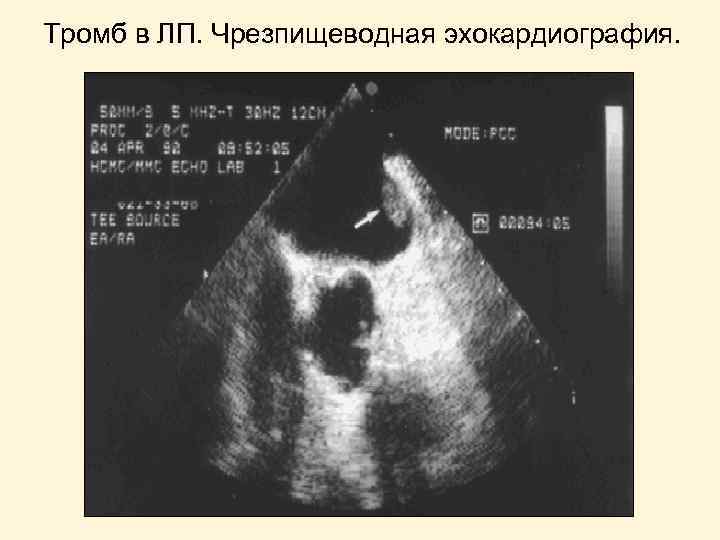

Тромб в ЛП. Чрезпищеводная эхокардиография.